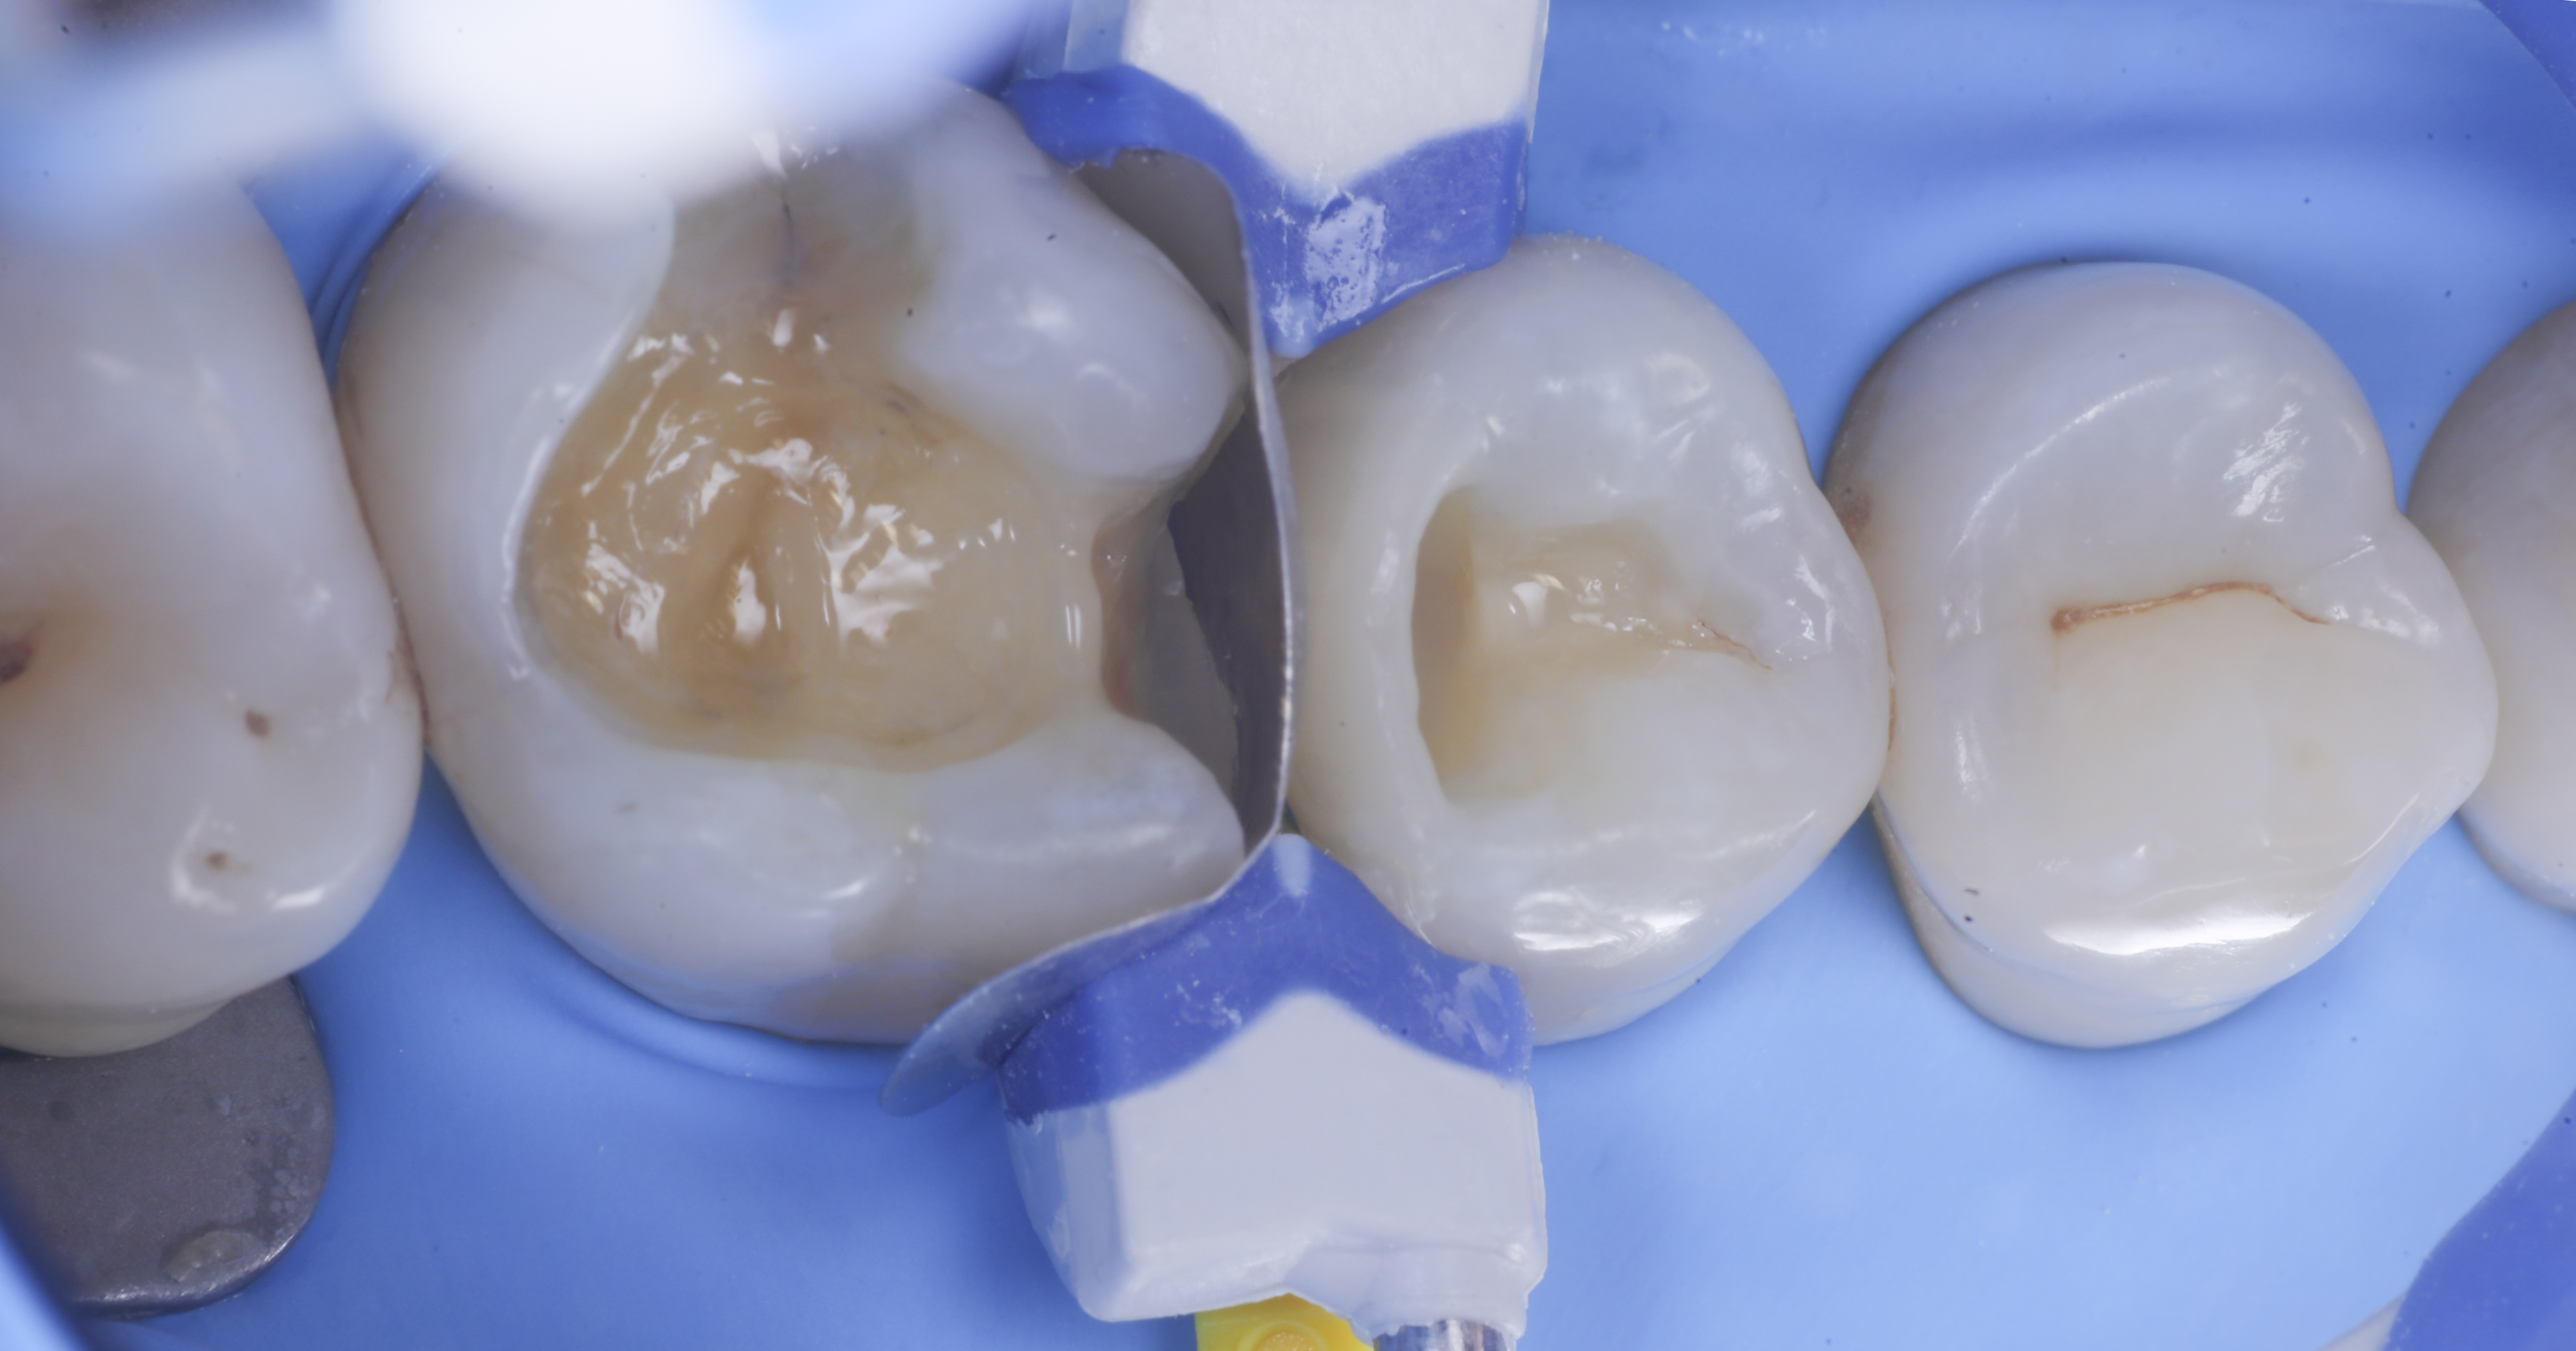

foto 2 Isolamento e aspetto delle cavità ultimate

foto 3 Aspetto vestibolare della cavità ultimate